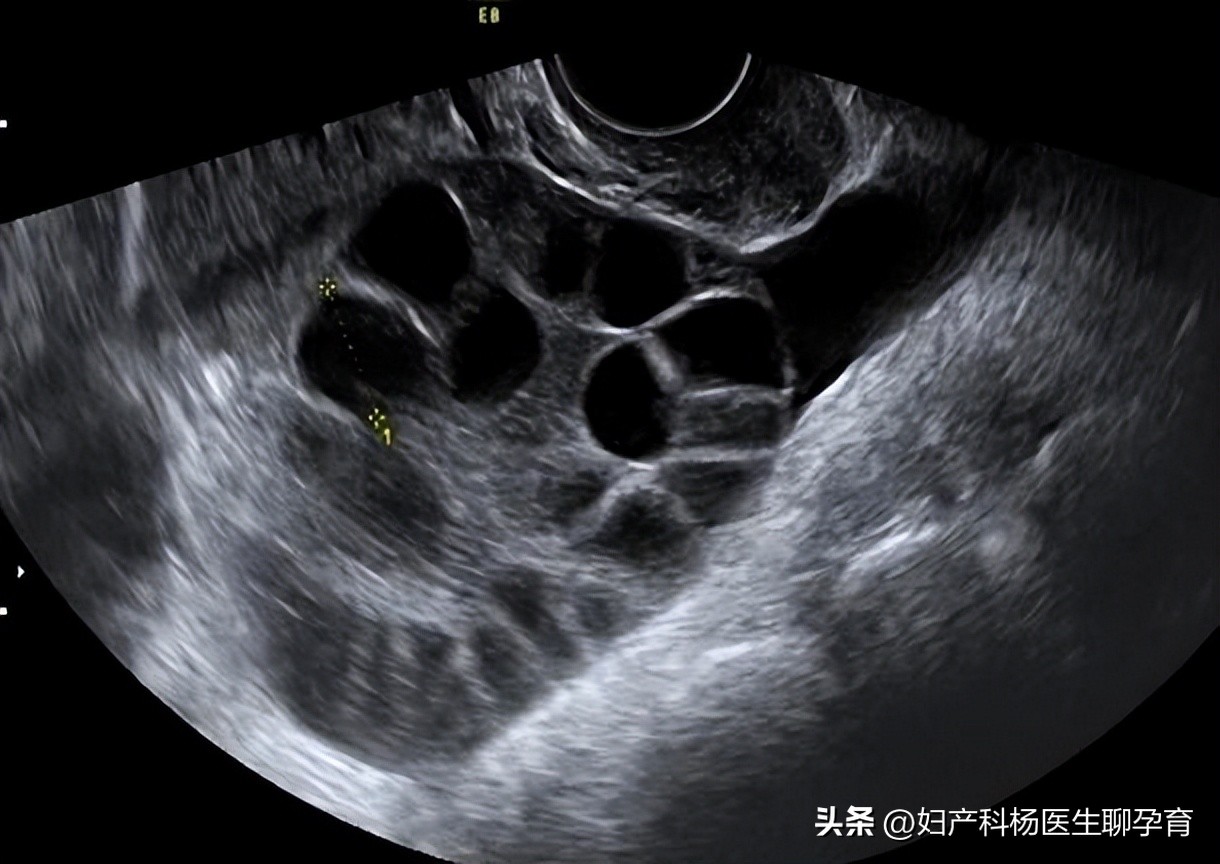

大学毕业后,刘女士了解了关于月经的知识,她不再认为自己的情况是正常生理反应。于是,她来到北京安太医院就诊,依据超声、激素检查以及月经稀发病史、肥胖、多毛、皮肤黑等体征表现,刘女士被确诊为多囊卵巢综合症。

不过,在进行超声检查时,北京安太医院的医生发现,刘女士的子宫内膜异常增厚。纵使她多次强调不想进行卵睾挫灭术,还要再拖一拖治疗。安太医生仍然规劝她及时治疗,因为,多囊卵巢不仅影响女性的孕育,还困扰女性的一生。